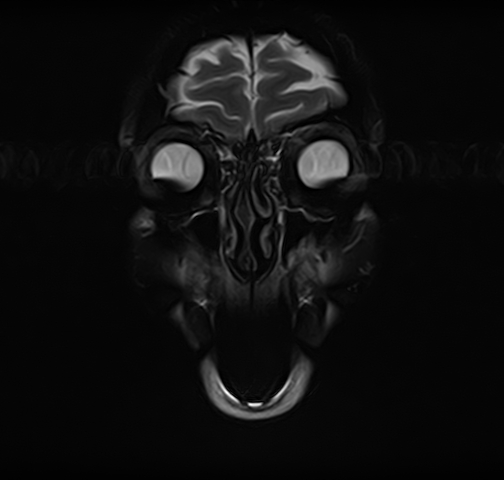

Височно-нижнечелюстной сустав является парным комбинированным суставом и имеет сложное строение. В него входят суставные ямки височной кости, суставные головки нижней челюсти и расположенные между ними хрящевые пластинки – мениски, выполняющие роль амортизаторов.

Чаще всего дисфункция височно-нижнечелюстного сустава обусловлена внутренним повреждением, смещением мениска и суставной головки нижней челюсти. Для определения степени смещения внутрисуставных структур выполняется функциональная проба с проведением МРТ в двух положениях:

Магнитно-резонансная томография является наиболее точным и эффективным методом диагностики поражения височно-нижнечелюстных суставов, так как позволяет получить детальную информацию о состоянии не только костей, но и связочного аппарата, хрящей, менисков, жевательных мышц, окружающих мягких тканей.

При проведении магнитно-резонансной томографии на изображениях визуализируются: височная кость, головка мыщелкового отростка нижней челюсти, суставная щель. Помимо костных структур МРТ позволяет оценить состояние мягких тканей – внутрисуставного диска и связочного аппарата височно-нижнечелюстного сустава, жевательных мышц.